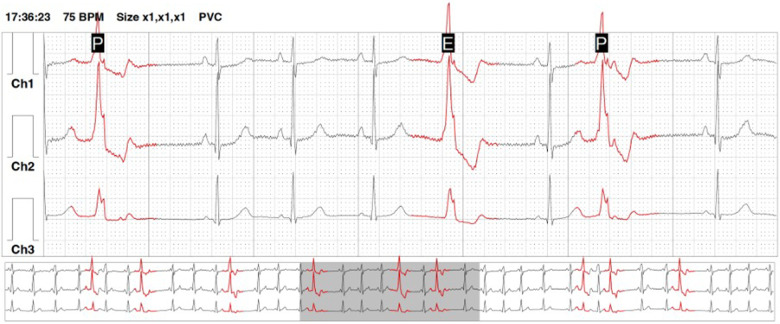

Figure 1.

An example of a holter-ECG recording showing premature ventricular contractions arranged into ventricular bigeminy episodes.